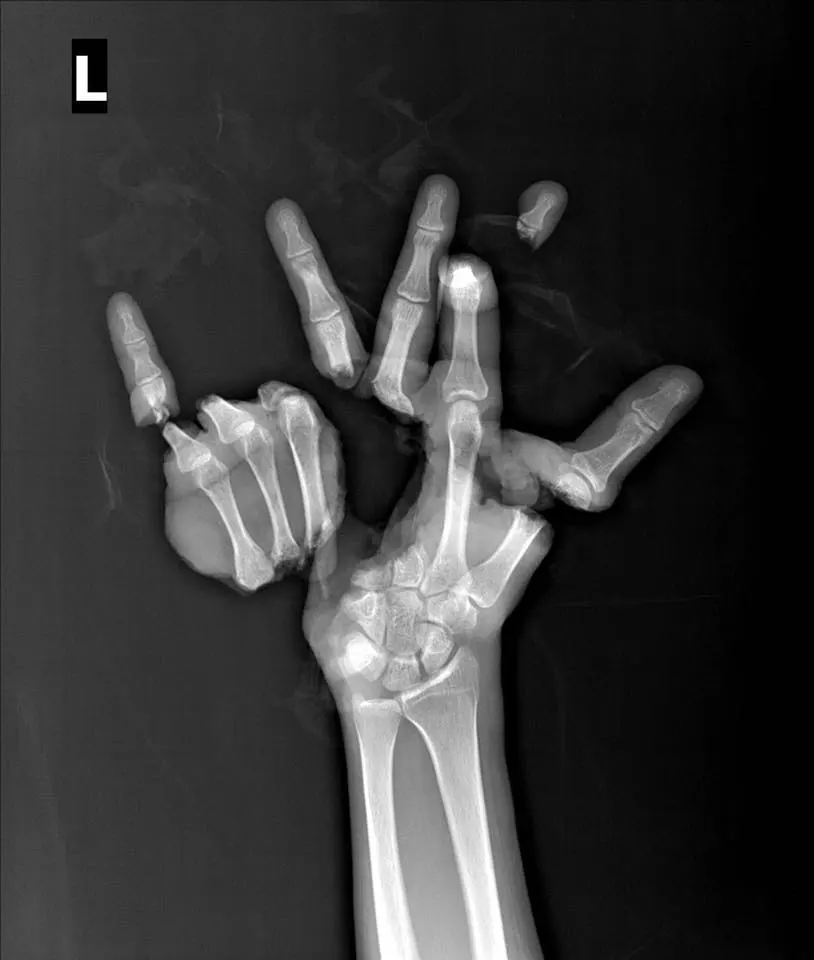

ฝีมือหมอ “หนุ่ม”ถูกเครื่องปั๊ม บดมือจนเละ หมอผ่าตัดต่อมือขาด นาน 10 ชั่วโมง จนสำเร็จ

กราบในฝีมือคุณหมอจริงๆ เมื่อผู้ใช้เฟซบุ๊ก ชื่อ Wichit Siritattamrong ได้ออกมาเผยแพร่โพสต์ ซึ่งเป็นเรื่องราวที่น่าเหลือเชื่อ เมื่อผู้ป่วยรายหนึ่ง ถูกเครื่องปั๊ม บดฝ่ามือขาดออกเป็น ชิ้นๆ นิ้วหัวแม่มือ ปลายนิ้วโคนนิ้วกลาง นางนิ้วก้อย และฝ่ามือขาด โดยคุณหมอได้ใช้เวลาในการผ่าตัด นานถึง 10 ชั่วโมง หมอไทยเก่งไม่แพ้ชาติใดในโลก โดยผู้ใช้เฟซบุ๊กดังกล่าว ได้ระบุข้อความเอาไว้ว่า...

คุณ หมอทำไม ไม่ต่อนิ้วชี้ ให้ผม? ผมฟังแล้วใจหายเลยครับ ไม่ถามสักคำว่าเราเหนื่อยมั้ย เป็นคำถาม ที่คนไข้ ถามผม หลังจาก การรักษาสิ้นสุดแล้ว ผมเลยถามกลับไปว่า วันที่คุณบาดเจ็บมา หมอเรียกให้คุณดูแผล คุณ ได้ดูบ้างหรือป่าวว่ามันบาดเจ็บขนาดไหน? ผมไม่ได้ดูครับ ผมกลัว ผมเลยจำเป็นต้องเปิดรูปบาดเจ็บครั้งแรกให้คนไข้รายนี้ดู หลังจาก ดูภาพเสร็จ ความรู้สึกเขาก็เปลี่ยนไปทันที แทนที่จะมาตำหนิผม กลายเป็นขอบคุณ ผม ที่ช่วยผ่าตัดให้เขา